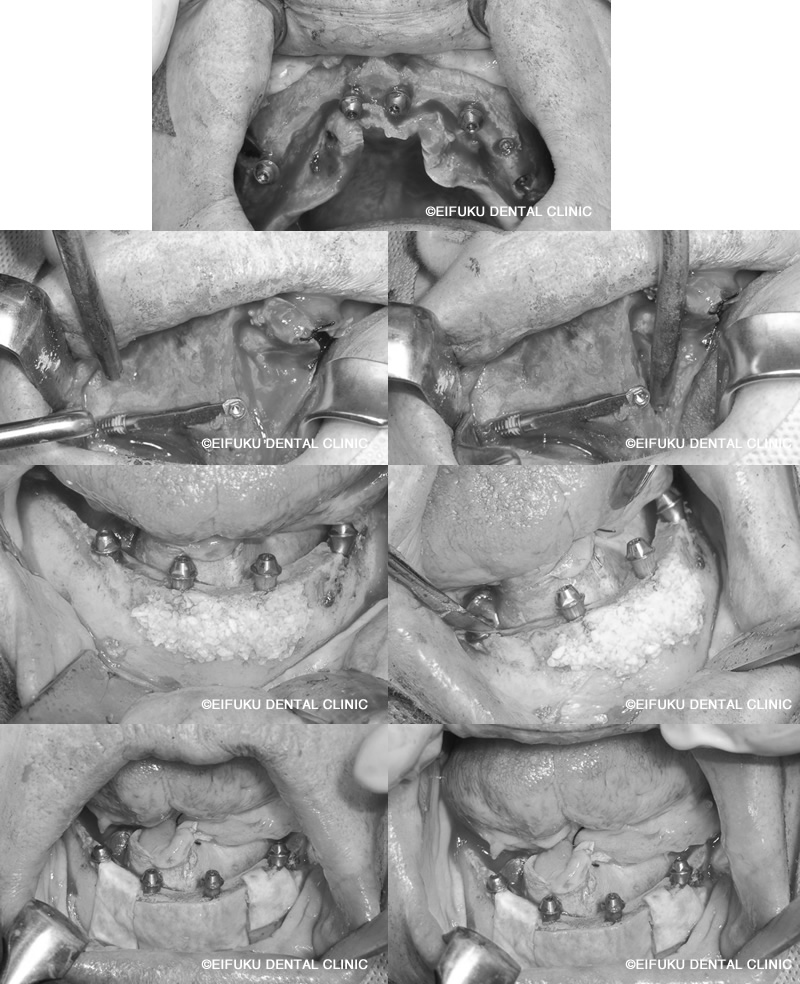

下の歯は4本、上の歯は5本インプラントを埋め込み、上下ともに1日で歯をセットしました。上の歯に関しては、単に5本埋入すればいいという問題ではありません。

ザイゴマインプラントによる即日オールオン4

| コメント | 「歯がボロボロで、このままでは何も噛めない」とお悩みの高齢70代のの女性の患者さんが、東京都内でインプラント治療を探されて当院に来院されました。 長年のむし歯と歯周病により、上も下もご自身の歯ではほとんど噛めない状態で、「入れ歯は合わないのですぐにしっかり噛みたい」というのが一番のご希望でした。当院ではまずCTによる精密検査を行い、骨量が大きく失われていた上顎には通常のインプラントではなく、頬骨を利用するザイゴマインプラントを選択しました。 下顎には4本のインプラントで全体の歯を支える「オールオン4(All-on-4)インプラント」を計画し、噛み合わせや負担のバランスを綿密に設計したうえで手術に臨みました。「手術が怖い」「痛みが心配」という不安をお持ちだったため、点滴でお薬を入れてうとうとリラックスした状態で治療が受けられる「静脈内鎮静法」を併用しました。 全身麻酔とは異なり意識は保ちながらも、手術中の恐怖心や痛みの記憶がほとんど残らず、長時間のインプラント手術でも安心して受けていただける方法です。手術当日に上顎ザイゴマインプラントと下顎オールオン4のインプラントを埋入し、十分な初期固定が得られたため、その日のうちに固定式の仮歯を装着しました。 「久しぶりに自分の歯で噛めているような感覚」「手術の記憶もあまりなく、あっという間に終わった」と、柔らかいものから少しずつお食事を楽しんでいただけるようになりました。ザイゴマインプラントやオールオン4は、総入れ歯や「歯がボロボロ」でお困りの方、骨が少なく他院でインプラントが難しいと言われた方でも、しっかり噛める状態を目指せる高度なインプラント治療です。 当院ではインプラント専門の歯科医師が、静脈内鎮静法を用いた負担の少ない手術と、長期的なメインテナンスまで見据えた治療計画で、東京都エリアの患者さんの「すぐに噛みたい」という願いにお応えしています。 |